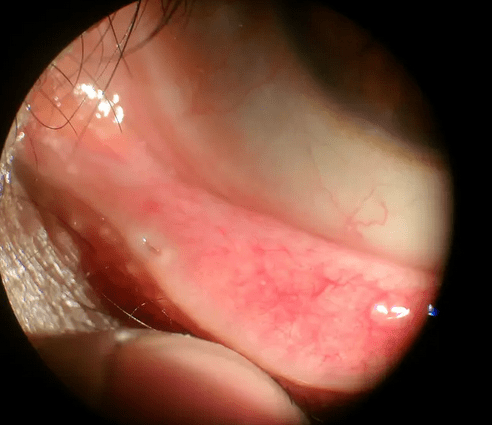

Všimli ste si, že na spodnej časti viečok sa nachádzajú malé dierky v rohu? A rozmýšľali ste načo vlastne slúžia? Nuž, nachádzajú sa na oboch viečkach a sú akýmsi lievikom, ktorý umožňuje slzám, ktoré sa nekotúľajú dole lícam, „cestovať“. Skončia napokon až vo vašom nose, čo vysvetľuje aj to, prečo si pri plači musíte fúkať nos.

Táto malá dierka sa odborne nazýva aj slzný bod. Je to v podstate tak, že dôvod prečo počas alebo po plači si potrebujete vyfúkať nos, je ten, že tekutiny sa dostávajú cez túto dierku priamo do nosa. Všetky slzy, ktoré sa neskotúľali dole lícami sa teda dostanú do slzného bodu. Tekutina sa následne odvádza cez nasolakrimálny kanál. A ak ste si ešte tieto malé dierky nevšimli, utekajte sa pozrieť do zrkadla.